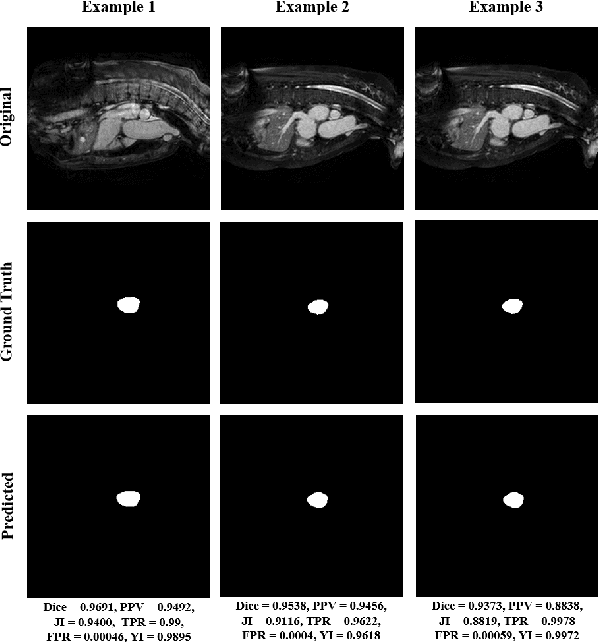

Abstract:Heart is one of the vital organs of human body. A minor dysfunction of heart even for a short time interval can be fatal, therefore, efficient monitoring of its physiological state is essential for the patients with cardiovascular diseases. In the recent past, various computer assisted medical imaging systems have been proposed for the segmentation of the organ of interest. However, for the segmentation of heart using MRI, only few methods have been proposed each with its own merits and demerits. For further advancement in this area of research, we analyze automated heart segmentation methods for magnetic resonance images. The analysis are based on deep learning methods that processes a full MR scan in a slice by slice fashion to predict desired mask for heart region. We design two encoder decoder type fully convolutional neural network models